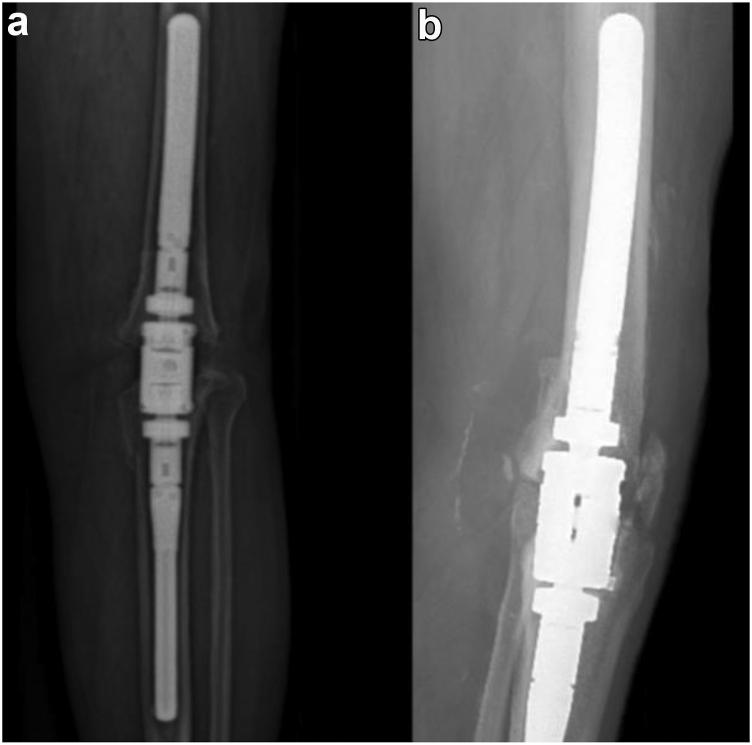

We retrospectively reviewed 8 patients implanted with an MKA at 2 institutions between 2016 and 2022. The mean age was 69.63 years, and 50.0% of patients were women. All patients were indicated for conversion to an MKA as the definitive treatment in the setting of treated chronic PJI after TKA, severe bone loss, and failure of the extensor mechanism not amenable to repair. Medical records and radiographs were reviewed.

No patients required incision and drainage or exchange of their MKA for PJI at mean 2-year follow-up. One patient required 2 revisions for mechanical failure of his implant at 5.0 and 6.4 years postoperatively.

MKA is a viable permanent alternative to AKA for patients with treated chronic PJI and dysfunctional extensor mechanism after TKA. The procedure restores leg lengths in the setting of severe bone and soft-tissue loss, therefore allowing patients to ambulate independently. Still, surgeons should be aware of the potential for mechanical failure requiring revision.